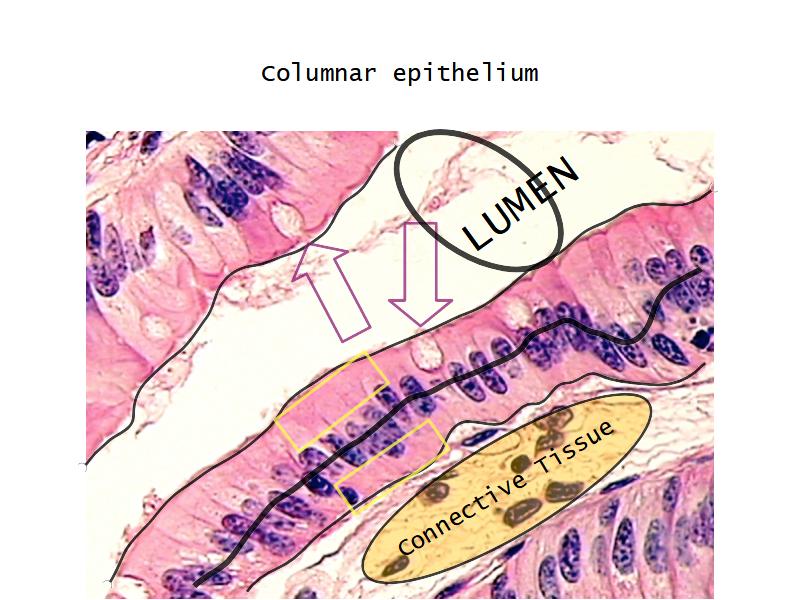

Respiratory epithelium

- Pseudostratified

- Ciliated

- Columnar

- Epithelium with

- 4 Cells

- Ciliated columnar cells

- Non-ciliated columnar cells

- Goblet cells

- Basal cells

Bronchi - Transitions

- Intrapulmonary bronchi

- Irregular cartilage

- Respiratory epithelium

- Glands

- Bronchioles

- Smooth muscle REPLACE cartilage

- Ciliated columnar > Ciliated cuboidal

- NO glands - goblet cells -> secretory cells